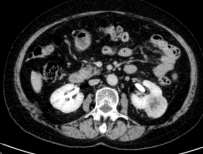

广泛开展腹腔镜下肾癌根治术、肾盂癌根治术、肾部分切除术、肾肿瘤剜除术、肾上腺肿瘤切除术、肾盂输尿管成形术、肾囊肿去顶减压术、输尿管上段切开取石术等。全腔镜下进行,创伤小、恢复快。

腹腔镜肾肿瘤剜除术(保肾) 腹腔镜肾癌根治术 腹腔镜肾盂癌根治术